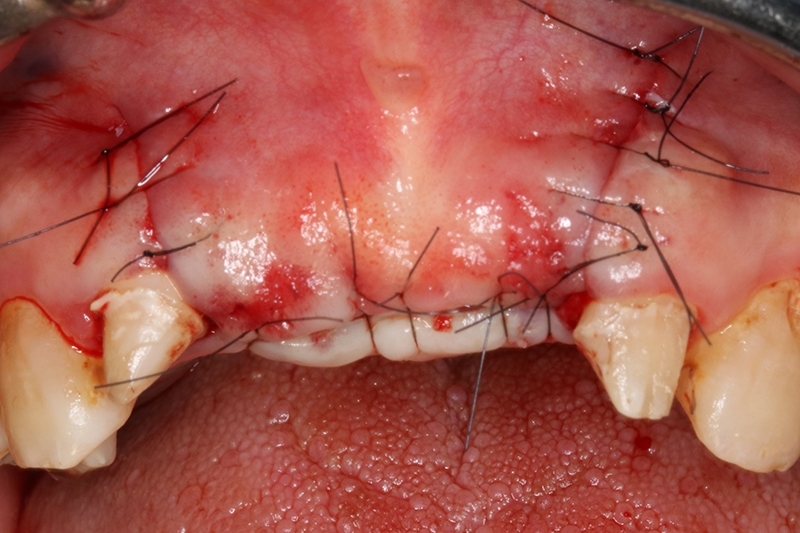

縫合傷口

2周後追蹤傷口,癒合良好。